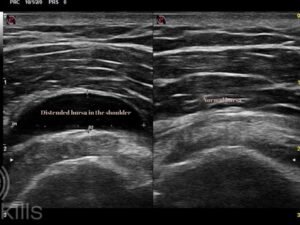

Shoulder bursitis is a common condition that causes pain, stiffness, and limited movement in the shoulder joint. It occurs when the bursa—a small, fluid‑filled sac that cushions and reduces friction between tissues—becomes irritated or inflamed.

In the shoulder, the most commonly affected bursa is the subacromial bursa, which sits between the rotator cuff tendons and the bony part of the shoulder (the acromion). When this bursa becomes inflamed, normal shoulder movements can become painful and restricted.

While the subacromial bursa is the most commonly affected in shoulder bursitis, several other bursae around the shoulder can also become inflamed. The subdeltoid bursa, which sits beneath the deltoid muscle, is often involved alongside the subacromial bursa, and the two are frequently described together as the subacromial–subdeltoid bursa. Less commonly, the subcoracoid bursa at the front of the shoulder can cause anterior shoulder pain, particularly with forward lifting or rotation movements. The subscapular bursa, located deeper at the front of the joint, may also become irritated and can sometimes communicate with the shoulder joint itself. In rarer cases, inflammation of the scapulothoracic bursae, found between the shoulder blade and chest wall, can cause pain along the upper back and may be associated with a grinding or snapping sensation. However, in clinical practice, most cases of shoulder bursitis involve the subacromial–subdeltoid bursa.